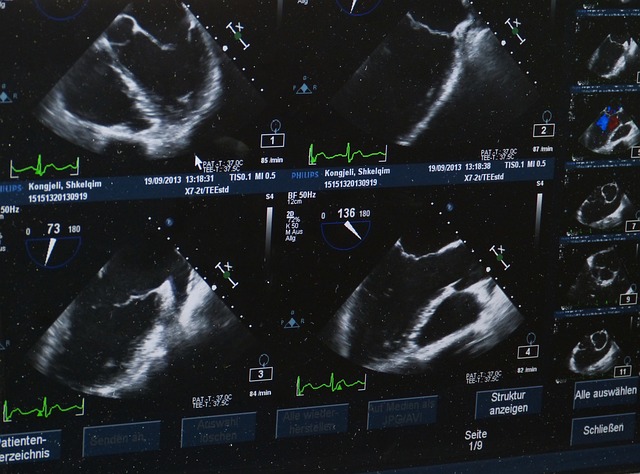

경동맥초음파는 경동맥의 상태를 평가하기 위해 초음파를 사용하는 비침습적 검사입니다. 고주파 음파를 이용하여 혈관 내부의 구조와 혈류 상태를 실시간으로 시각화할 수 있습니다. 이를 통해 경동맥의 벽 두께, 혈관 내 플라크의 존재 여부, 그리고 혈류의 속도를 측정할 수 있어, 심혈관 질환의 조기 진단에 유용합니다.

경동맥초음파 검사는 환자가 누운 상태에서 진행됩니다. 검사자는 초음파 프로브에 젤을 바르고, 이를 환자의 목 부위에 대고 초음파 영상을 얻습니다. 이 과정에서 환자는 편안하게 숨쉬고 움직이지 않도록 해야 합니다. 검사는 보통 15-30분 정도 소요되며, 통증 없이 안전하게 진행됩니다.

경동맥초음파의 결과는 경동맥 벽의 두께, 플라크의 유무, 혈류 속도 등을 바탕으로 해석됩니다. 경동맥의 내막-중막 두께(IMT)가 증가하거나 플라크가 발견되는 경우, 심혈관 질환의 위험이 높다고 판단할 수 있습니다. 혈류 속도의 변화를 통해 협착의 정도도 평가할 수 있으며, 이를 바탕으로 적절한 치료 계획을 수립합니다.